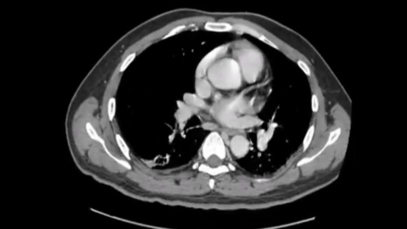

What are the results of a CT scan of the abdomen and pelvis? An abdominal and pelvic CT scan can diagnose obstructions, kidney stones, hernias, masses, tumors, infections, aneurysms and many other problems. How do you read a CT scan report? One of the recommended approaches includes the following steps: Examine anatomical borders of […]